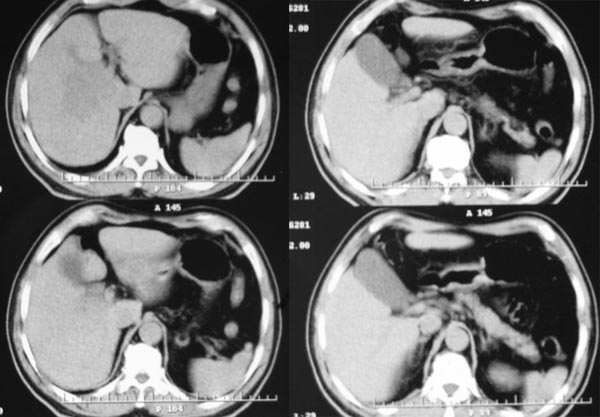

动脉期

2、动脉期:病灶边缘强化明显,明显高于肝实质,中间未强化为坏死区

2.病灶特点:平扫呈低密度,密度不均,中央呈更低密度;动脉期病灶周围强化较明显,高于正常肝组织,低于同层主动脉密度,中央坏死区未见明显强化;门静脉期,病灶呈低密度,低于正常肝组织密度。

早期强化不是很明显,血供不是很丰富,与肝实质相比还是呈快进快出的特点,中心裂隙样坏死,支持原发性肝癌。